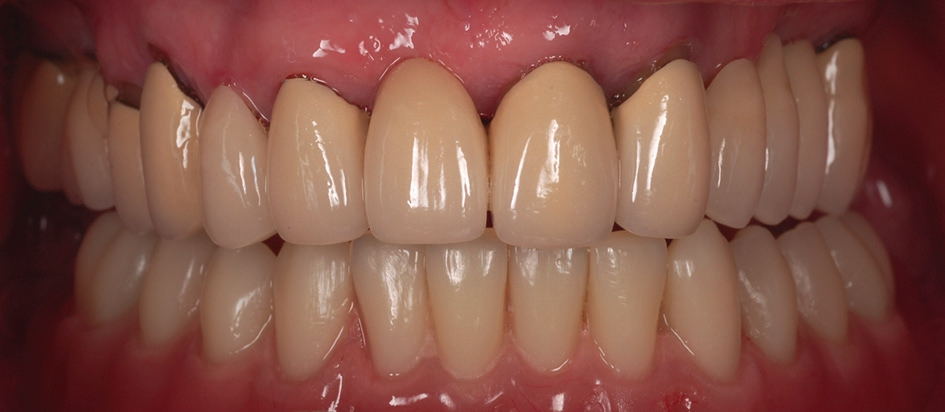

Als dritte Behandlungsoption wurde eine bedingt herausnehmbare Rekonstruktion gewählt, die auf den systemeigenen PS MultiPlus-Abutments befestigt wurde (Abb. 16 und 17). Grundlage für die bedingt herausnehmbare Brücke war ein mittels Selective Laser Melting hergestelltes Kobalt-Chrom Gerüst (EOS; Electro Optical Systems München, Deutschland). In unserem Patientenfall konnte eine sehr gute, passgenaue Herstellung des Metallgerüsts erfolgen (Abb. 18). Das Gerüst wurde mittels Komposit (anaxblend big block dentin und big block enamel, anaxdent GmbH, Stuttgart, Deutschland) verblendet (Abb. 19a und b). Die Schraubenkanäle wurden nach Einsetzen der Suprakonstruktion mit Komposite (EcuSphere-Carat, DMG Chemisch- Pharmazeutische Fabrik GmbH, Hamburg, Deutschland) verschlossen (Abb. 20). Das klinische Endergebnis war für den Patienten sehr zufriedenstellend, da die Rekonstruktion sehr natürlich und ästhetisch gestaltet war (Abb. 21).